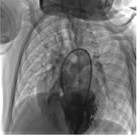

图2 封堵后无残余分流

应用12 mm封堵器堵闭室间隔缺损(图2)。患儿在术前曾患感冒,术中痰鸣音较多,血氧饱和度曾一度下降。经面罩给氧辅助呼吸后,患儿的血氧饱和度有所改善,但释放封堵器后出现严重的低氧血症,血氧饱和度(SaO2)为30%。经呼吸机辅助呼吸治疗后,低氧血症无改善。